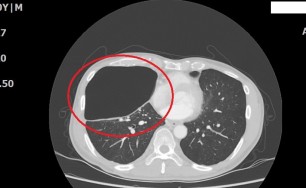

숨케어한의원에서는 전화예약을 받고 있습니다. 내원시 엑스레이, CT사진, 폐기능검사지를 가지고 오시면 자세한 상담이 가능합니다.